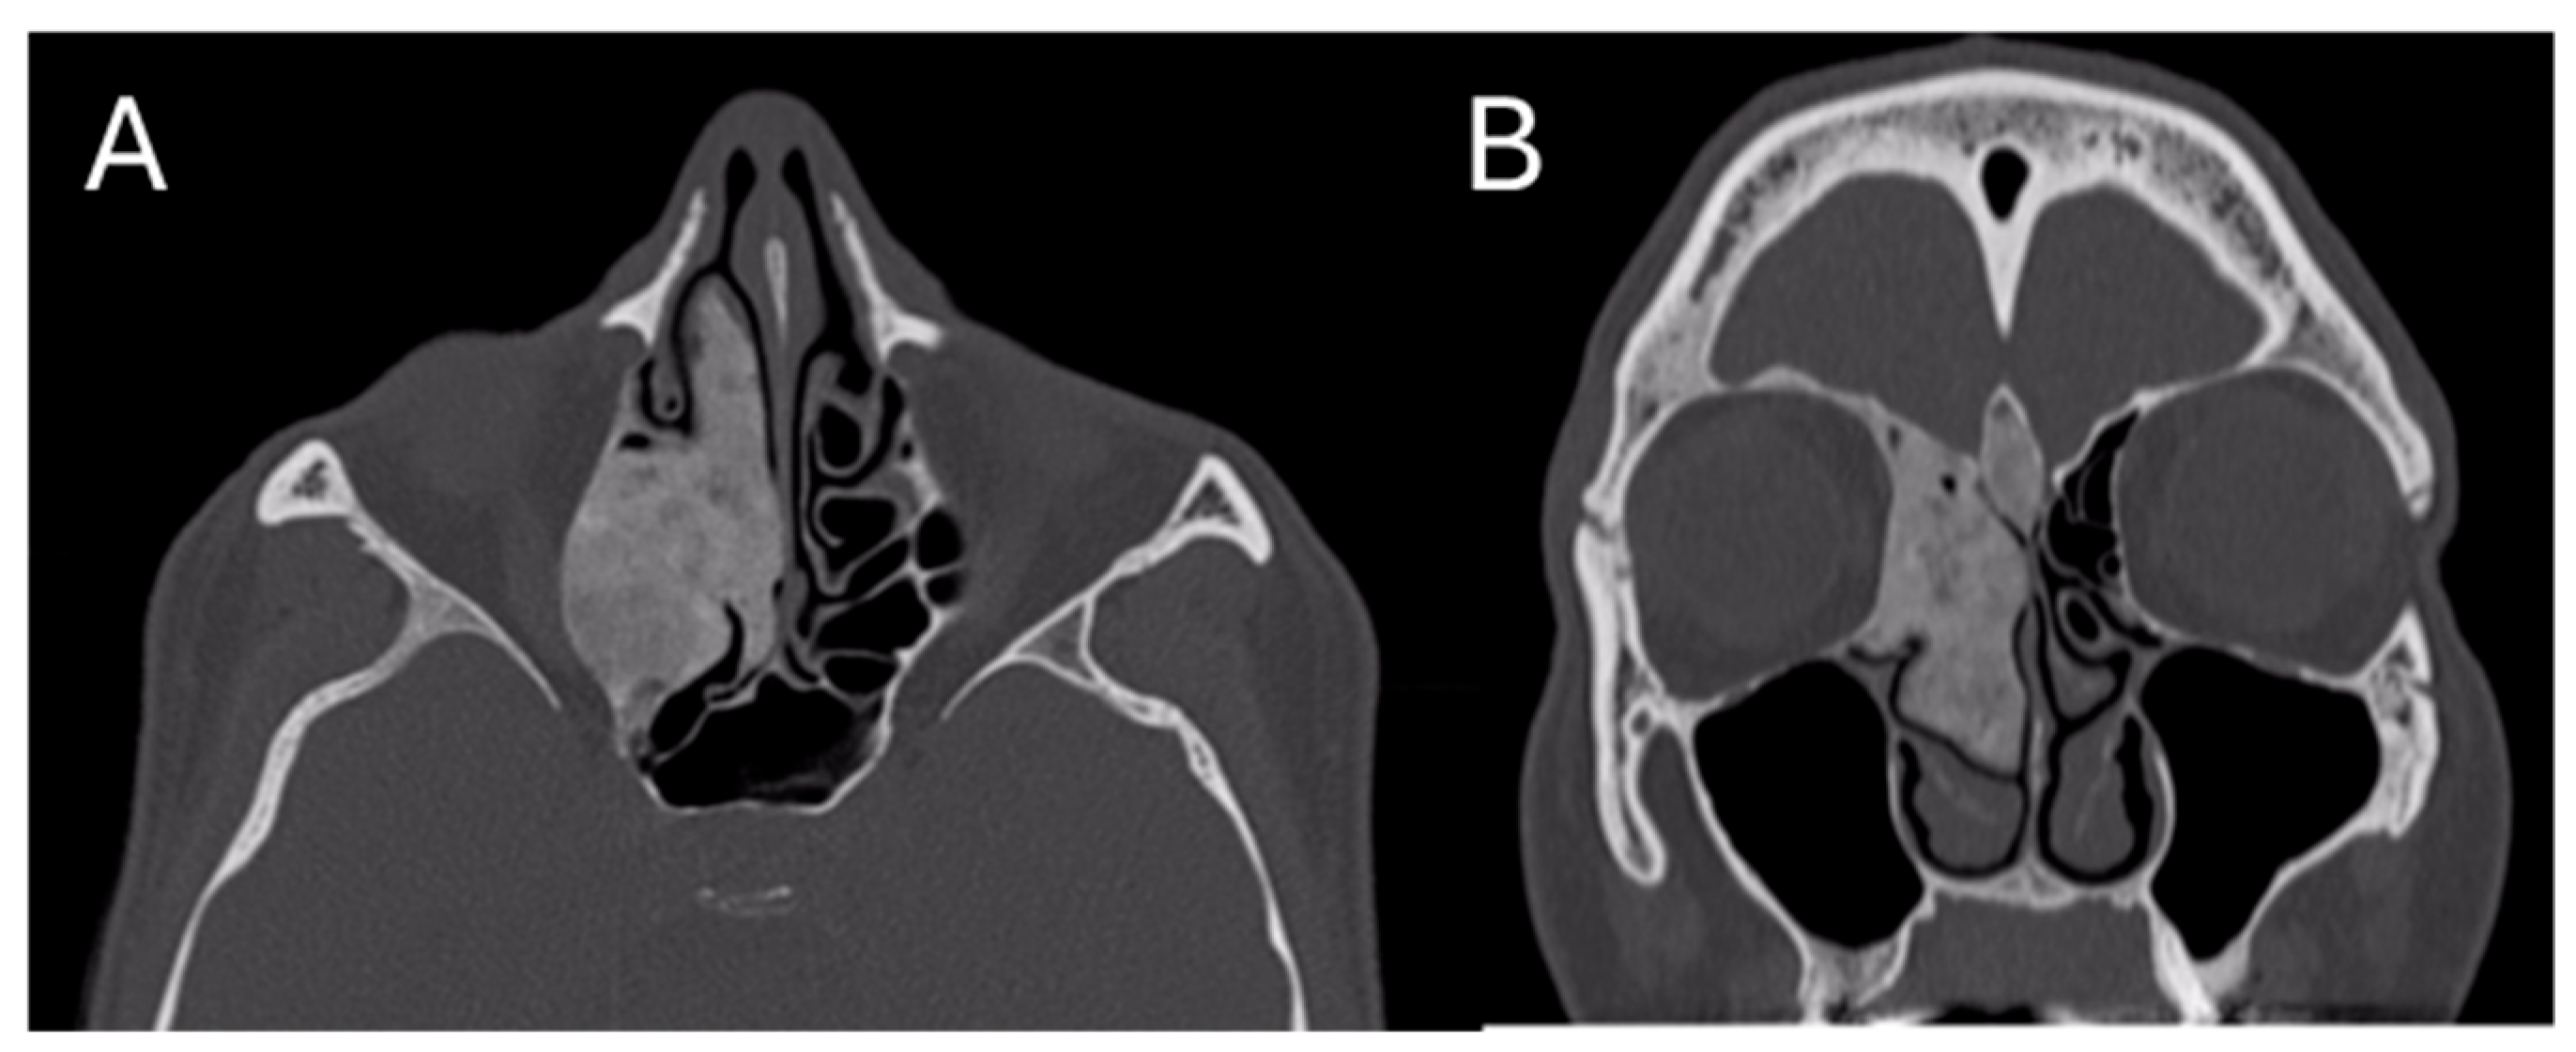

After the surgical intervention, a skull CT scan was performed, revealing a near-complete removal of the lesion (Figure 6).

Figure 6. Post-operative CT image of Patient 2. Two axial cuts of the post-operative CT scan are appreciatedat the same level as those shown in Figure 3 to demonstrate the outcomes of the surgical removal. (A) the absence of the lesion localized at the ethmoidal level (B) The absence of the lesion localized in the right frontal sinus.